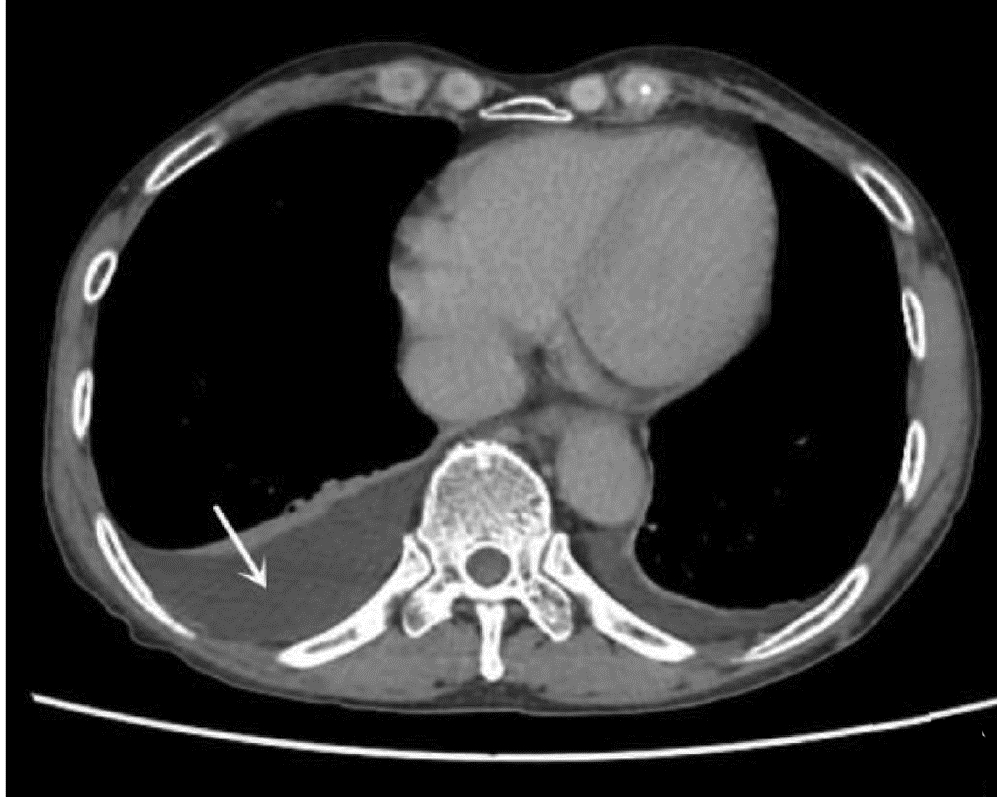

肿块型自身免疫性胰腺炎与胰腺导管腺癌的超声及超声造影表现分析

欧阳向柳, 韩云霞, 郑立春, 赵英春, 申新宇, 张文军, 王艳滨

2022, 38(6): 1351-1355. DOI: 10.3969/j.issn.1001-5256.2022.06.025

摘要(1431) HTML (553) PDF (3738KB)(51)

摘要:

目的  探讨超声及超声造影对肿块型自身免疫性胰腺炎(AIP)与胰腺导管腺癌(PDAC)的鉴别诊断价值。  方法  回顾性分析2015年1月—2020年12月唐山市工人医院确诊的11例肿块型AIP患者的临床资料及常规超声、超声造影资料,分析其特征性表现,并与23例PDAC患者的资料进行对比,计数资料两组间比较采用χ2检验。  结果  11例肿块型AIP超声造影的诊断准确性为63.64%,均为单发病灶,且均低回声,在边界清晰、形态规则、胰管扩张或截断、血流信号方面所占比例分别为54.55%、63.64%、18.18%、36.36%,而PDCA组分别为30.43%、34.78%、78.26%、21.74%,两组间是否伴胰管扩张或截断方面存在统计学差异(χ2=11.089,P<0.05),其余指标均无明显统计学差异(P值均>0.05)。超声造影中7例(63.64%)肿块型AIP动脉期呈高增强,4例(36.36%)呈等增强,静脉期5例(45.45%)呈高增强、6例(54.55%)呈等增强;23例PDAC中22例(95.65%)病灶在动脉期及静脉期均呈低增强,两者动、静脉期强化方式差异均有统计学意义(χ2值分别为30.345、30.084,P值均<0.05)。  结论  超声造影检查增强模式及是否伴胰管扩张或截断方面在肿块型AIP与PDCA的鉴别诊断中具有较高的价值。